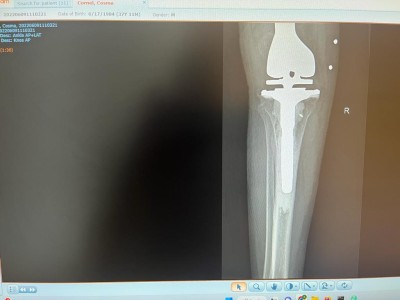

ORTOPEDIE-TRAUMATOLOGIE: Interventie chirurgicala de protezare segmentara a genunchiului la un pacient tanar cu fractura deschisa la nivelul genunchiului

La CLINICA DE ORTOPEDIE-TRAUMATOLOGIE a spitalului nostru a fost efectuata o interventie chirurgicala aparte si cu un grad ridicat de dificultate, la pacientul C.C., in varsta de 36 ani, din Bistrita. Acesta a suferit in luna noiembrie 2021 o fractura deschisa tip III B la nivelul femurului distal, fiind operat in Urgenta cu fixator extern, de catre o echipa medicala (dr. COSTE REMUS, dr. DRAGHICIOIU HOREA, dr. MUBARAK FADOL, as. GAVRA MONICA) condusa de dr. CHIREA MARIUS, medic primar ORTOPEDIE-TRAUMATOLOGIE .

La 7 luni de la accident s-a prezentat in serviciul nostru cu anchiloza marcata a genunchiului si defect osos sever la nivelul femurului distal.

"Defectul osos mare de la nivelul femurului distal impun o reconstructie a genunchiului cu endoproteza segmentara pentru defect femural mare pe care impreuna cu echipa mea (dr. COSTE REMUS, dr. DRAGHICIOIU HOREA, dr. MUBARAK FADOL, as. GAVRA MONICA) am efectuat-o in luna iunie 2022. Lipsa mare de os de la nivelul femurului distal am inlocuit-o cu un sistem GMRS Stryker.